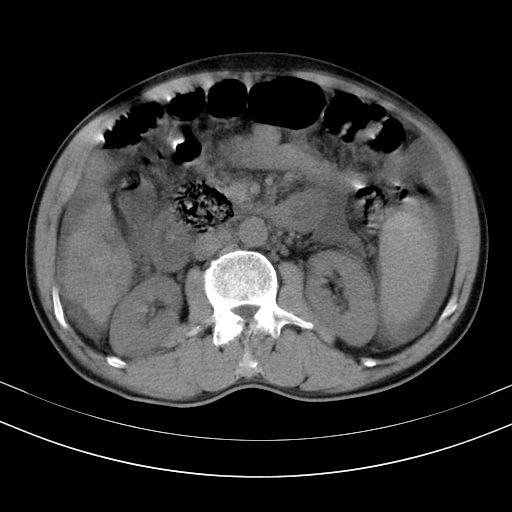

以下是引用随光逐影在2010-2-28 10:23:00的发言:[br]1)考虑肝癌;建议行ct增强扫描检查。2)肝硬化,脾大,腹水。3)慢性胆囊炎。

以下是引用dyqct在2010-2-28 16:44:00的发言:[br][quote]以下是引用随光逐影在2010-2-28 10:23:00的发言:[br]1)考虑肝癌;建议行ct增强扫描检查。2)肝硬化,脾大,腹水。3)慢性胆囊炎。